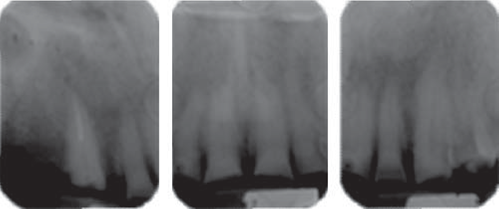

Este reporte documenta el tratamiento de un paciente masculino de 68 años de edad. Comenta tener dificultades masticatorias y digestivas debido a importante desgaste dental, se dice incómodo al sonreír; no refirió padecimientos sistémicos, fumó durante ocho años, diagnosticado con hipertensión arterial controlada. Se observa atrición generalizada, ausencia de dientes 14, 15, 16, 46 y periodonto sano (Figuras 1a4). Los dientes 13 y 37 presentaban tratamiento de conductos y periápice sano, sin restauración (Figura 5).

Para cuantificar la reducción de DVO, se examinó el perfil facial y la estética mediante análisis fotográfico y vídeo (Figuras 6y7). Además de realizar un cuidadoso análisis del montaje de los modelos diagnósticos en articulador semiajustable (Figura 8). También se examinó el esquema oclusal (presentaba relación borde a borde) y la estructura dental con la que se contaba (Figura 3). La revisión dinámica fue clave para determinar que el paciente exhibe una línea de sonrisa alta (Figura 9).

Mediante evaluación radiográfica de la relación corona-raíz, se realizó el alargamiento de la corona en el sextante anterosuperior para exponer suficiente estructura dental y lograr una retención adecuada para las restauraciones finales (Figuras 16a22).